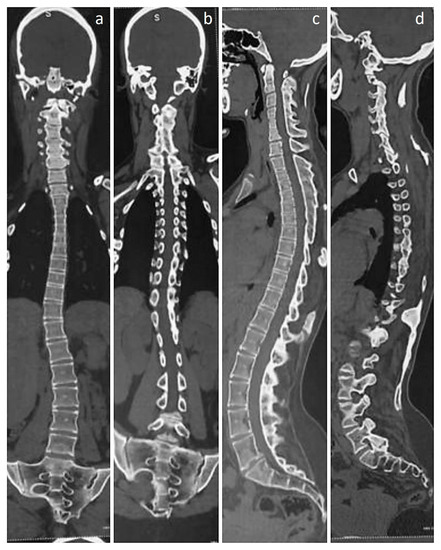

Figure 4. Three-dimensional CT images of the pelvis. (a,b) Images demonstrate a tilted pelvis, in compensation for the thoracolumbar scoliosis. (bd) Posterior and oblique views, showing a heterotopic bony mass arising from the left ischium and projecting upwards. As such, the hip joints are unaffected by movement-restricting heterotopic ossifications; however, asymmetry of femoral heads can be noted, with the right femoral head appearing larger than the left. While hip rotations were restricted to a certain extent, no other heterotopic ossifications were observed in the lower limbs. Despite the significant impairment of mobility caused by widespread ossifications in the spine and the right upper limb, the patient can walk and manage her daily tasks with assistance. Although genetic sequencing was not performed to ascertain the mutation, classical signs were confirmatory of the diagnosis and currently, treatment is focused on mitigating inflammation with the use of nonsteroidal anti-inflammatory drugs and reducing pain [4]. While there is no definite treatment that can reverse the effects of the disease [5], Kaplan et al. have provided a comprehensive overview of the present medical management strategies, which serves as a guide for healthcare professionals treating individuals with FOP [6]. However, it should be noted that there could be progressive development of heterotopic bone at multiple sites, eventually leading to a significant loss of mobility [7,8]. Hence, it is important for patients to work closely with healthcare providers to manage symptoms and maintain the highest possible level of function and quality of life. While ongoing research on novel drugs targeting the FOP process continues, it is essential for clinicians to be aware of the initial diagnostic features of the condition, such as malformed great toes, even prior to the onset of heterotopic ossification [9]. Doing so gives a chance for early genetic consultation and testing. If signs favor a diagnosis of FOP, preventing injuries and minimizing iatrogenic harm is of critical importance, as injury sites are known to be susceptible to the cascade of events that lead to heterotopic ossification [10].